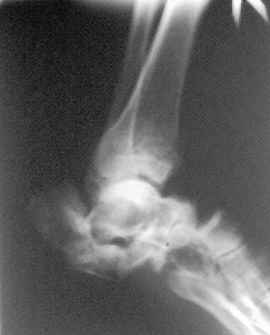

Отправляю снимки(свежие)и фото стоп.

С уважениемД.Б.

Присоединяюсь к мнению Я.Одесского о необходимости аксиальных снимков и, наверное, сразу снимков по Бродену (через каждые 10 градусов внутренней ротации стопы). Кроме этого необходима КТ. Она позволит уточнить срослись переломы или нет. Соответственно и тактика: если не срослись можно попробовать АВФ; если срослись -артродез.

С левой стопой дело похуже. Нужен прямой снимок, да и боковой не помешает повторить на всю стопу, ну и плюс аксиальный. Готовтье аппарат.